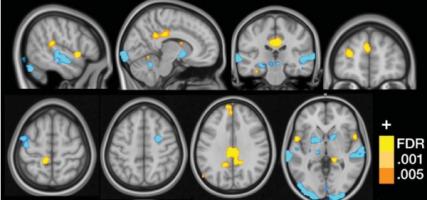

L'agression/agressivité est un comportement qui se retrouve chez l’ensemble des animaux et « qui façonne les vies humaines depuis les premières rencontres dans les cours d'école jusqu'à l'expression la plus extrême d'un conflit armé et mondial », écrivent les chercheurs dans leur communiqué. Mieux cerner les origines de l’agression dans le cerveau apporte donc une compréhension indispensable de nos comportements. Ces chercheurs identifient un groupe de neurones clé, jusque-là quasiment inconnu, situé dans le noyau prémammillaire de l'hypothalamus, une zone du cerveau bien préservée sur le plan évolutif qui contrôle plusieurs de nos pulsions fondamentales.

Contrôler la violence -par la lumière ? Sur des souris mâles, les chercheurs constatent que les animaux qui montrent de l'agressivité lorsqu'un nouveau mâle est placé dans leur cage d'accueil présentent des neurones « PMv » plus actifs. En activant ces PMv grâce à l'optogénétique donc à l'aide de lumière, ils parviennent à induire un comportement agressif dans des situations où l’animal n'attaque pas normalement et en inhibant ces PMv, à interrompre une attaque/agression en cours. Les effets de ces manipulations semblent durables, car les changements de comportements liés à l'activité PMv durent jusqu'à 2 semaines. Enfin, la cartographie de ces PMv montre que ces neurones peuvent à leur tour activer d'autres zones du cerveau, telles que les centres de la récompense.